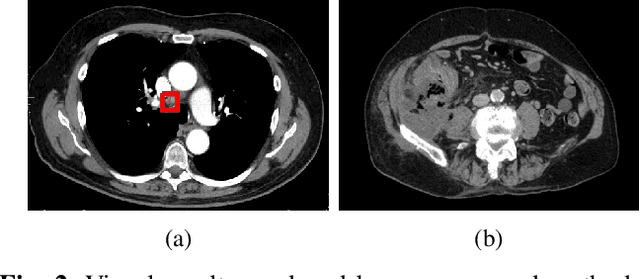

Abstract:The diagnosis of the presence of metastatic lymph nodes from abdominal computed tomography (CT) scans is an essential task performed by radiologists to guide radiation and chemotherapy treatment. State-of-the-art deep learning classifiers trained for this task usually rely on a training set containing CT volumes and their respective image-level (i.e., global) annotation. However, the lack of annotations for the localisation of the regions of interest (ROIs) containing lymph nodes can limit classification accuracy due to the small size of the relevant ROIs in this problem. The use of lymph node ROIs together with global annotations in a multi-task training process has the potential to improve classification accuracy, but the high cost involved in obtaining the ROI annotation for the same samples that have global annotations is a roadblock for this alternative. We address this limitation by introducing a new training strategy from two data sets: one containing the global annotations, and another (publicly available) containing only the lymph node ROI localisation. We term our new strategy semi-supervised multi-domain multi-task training, where the goal is to improve the diagnosis accuracy on the globally annotated data set by incorporating the ROI annotations from a different domain. Using a private data set containing global annotations and a public data set containing lymph node ROI localisation, we show that our proposed training mechanism improves the area under the ROC curve for the classification task compared to several training method baselines.